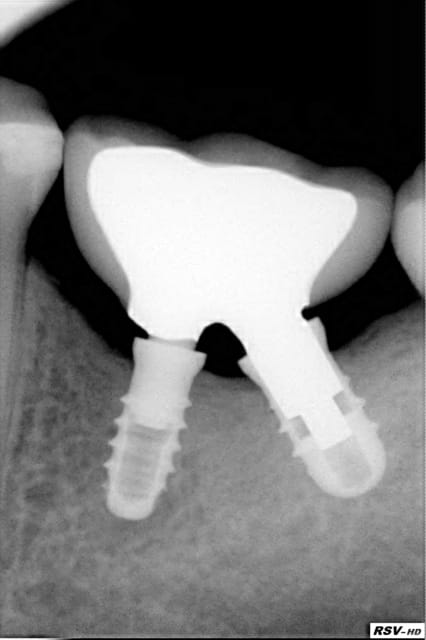

Mais visez la rx ça c'est 2 implants une dent!

Replacement of a molar with 2 narrow diameter dental implants

in Implant Dentistry Vol 21,Number 1 2012

Ziv Mazor,Adi lorean,Eitan Mijirisky,Liran Levin